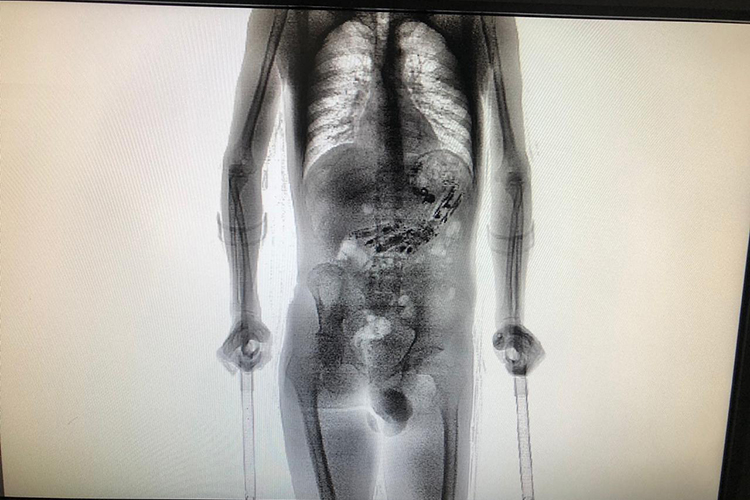

Um apenado precisou passar por uma cirurgia após agentes descobrirem que ele carregava telefones celulares dentro do estômago. O caso foi em Santa Catarina, quando ele retornou na terça-feira de uma saída temporária à Colônia Penal Agrícola de Palhoça, na Grande Florianópolis. O preso foi submetido a um scanner corporal porque o detector havia sinalizado a presença de metal no corpo.

Diante da confirmação de que havia materiais no estômago, ele teve de passar por uma cirurgia. Surpreendentemente, foram encontrados nada menos do que dez aparelhos celulares, além de outros 52 invólucros com cabo USB, isqueiro, chips de celular, drogas, entre outros objetos. A informação é do Departamento de Administração Prisional (Deap).